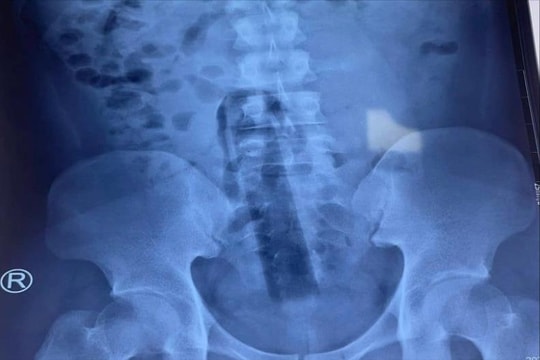

Cấp cứu nam thanh niên tự nhét ống cao su dài 1m vào bàng quang